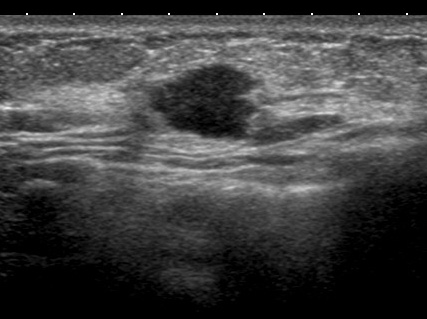

線維腺腫っぽく見えても癌 case.3

これなんかも(左)癌なのだから、やはり「なのは」さんの所見を「線維腺腫だ!間違いない」などというのが如何に無知なことか!

典型的な「線維腺腫(実際に生検で線維腺腫と確認)」と典型的な癌「私のcat.7」を提示します。

左と右、どちらが線維腺腫でどちらが癌なのか?当ててください(皆さんなら簡単ですね? 引っかけはありません)

このくらい典型(私cat. 2)ならば画像だけで「線維腺腫で大丈夫です」と言えるのです。

♯逆にこれくらい典型(私cat. 7)ならば画像だけで癌と言い切ってもいいでしょう。